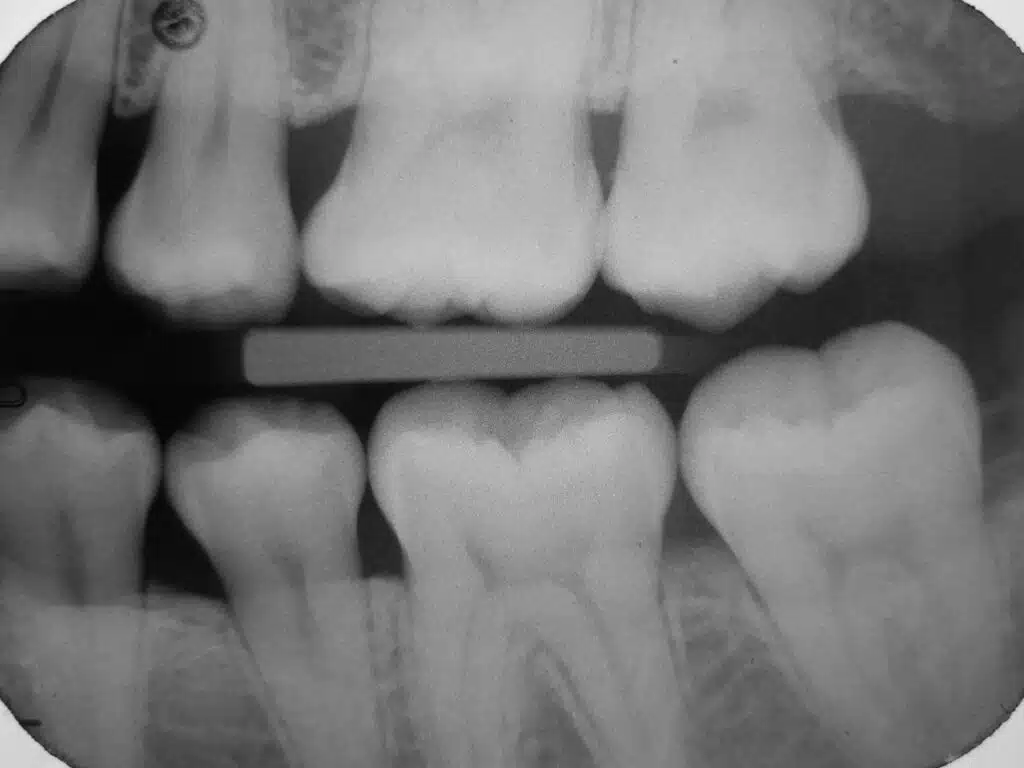

When patients experience tooth pain but X-ray normal, it often reflects the limitations of imaging. X-rays are excellent for detecting many structural changes in teeth and bone, but they do not always capture early inflammation, fine cracks, or bite-related stress.

Tiny cracks can cause sharp pain when biting or releasing pressure. These are often too fine to show on standard X-rays. This is one reason a cracked tooth can be easy to miss early on. For general background, see the American Association of Endodontists on cracked teeth.

The ligament supporting the tooth can become inflamed from clenching, grinding, or bite imbalance. This can create soreness even when the X-ray appears normal.

The pulp inside the tooth may be irritated before any visible damage appears. Sensitivity to temperature or lingering discomfort are common early signs—even when imaging looks unremarkable.